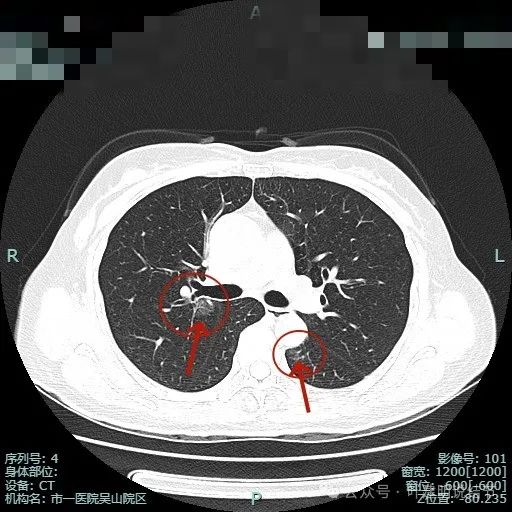

病灶1边缘部分的样子;病灶表面欠光滑,有血管贴边。整体轮廓与边界清楚。

病灶2血管与病灶间没有间隙,表面浅分叶,并贴着斜裂。

斜裂略有牵拉向病灶,灶内密度稍不均,边缘有短细小毛刺征。